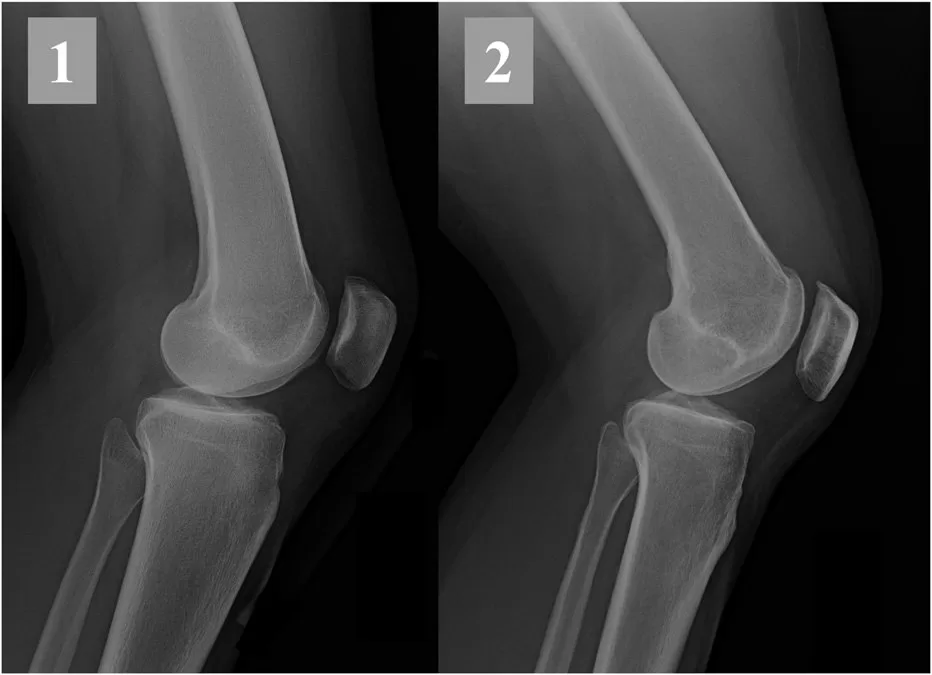

Even the apparently straightforward question of “does this knee have arthritis on plain radiographs” turns out to depend significantly on which view was taken and which grading system was used. Duncan-Burnham et al.’s 2015 systematic review of Level I studies in Arthroscopy found that the 45° flexion posteroanterior (PA) view is more sensitive than the standing anteroposterior (AP) view for detecting severe tibiofemoral osteoarthritis, with no clinical difference in sensitivity between the Kellgren-Lawrence and joint space narrowing grading systems, although the joint space narrowing system may be more specific for ruling in severe medial-compartment osteoarthritis (Duncan-Burnham et al., 2015). The practical implication for records review is straightforward: if the radiographs in the file were obtained with a less-sensitive view, the absence of severe arthritis on those films does not exclude severe arthritis. Reaching that conclusion requires either advanced imaging or a repeat radiographic study with the appropriate technique. A reviewer who does not know the published performance of each radiographic view will read the films at face value and miss the disconnect between what the imaging method can detect and what the clinical question requires.

- Duncan ST, Khazzam MS, Burnham JM, Spindler KP, Dunn WR, Wright RW. Sensitivity of standing radiographs to detect knee arthritis: a systematic review of Level I studies. Arthroscopy. 2015;31(2):321-328. DOI | PubMed | Full-Text PDF

Every imaging modality has known sensitivity and specificity limits, and the unstructured clinical record rarely makes those limits explicit. A radiograph that shows no fracture does not exclude a fracture. An MRI that shows a tear does not establish the tear is symptomatic. Different views and grading systems materially change diagnostic performance. For example, the 45° flexion PA radiograph is more sensitive than the standing AP for detecting severe tibiofemoral osteoarthritis (Duncan-Burnham et al., 2015), and MRI sensitivity for meniscal ramp lesions ranges from 53.9% to 84.6% (Arner, Burnham et al., 2017). A reviewer who reads imaging at face value, without the published diagnostic performance data, will produce opinions that do not survive cross-examination.